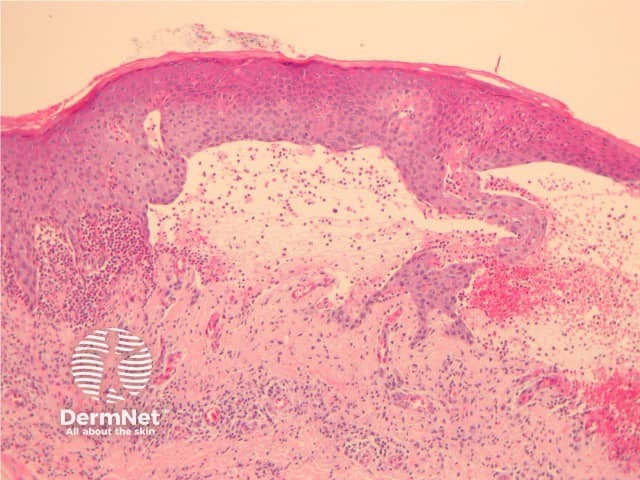

The histological features of bullous pemphigoid are:

Subepidermal bulla

Direct immune fluorescence